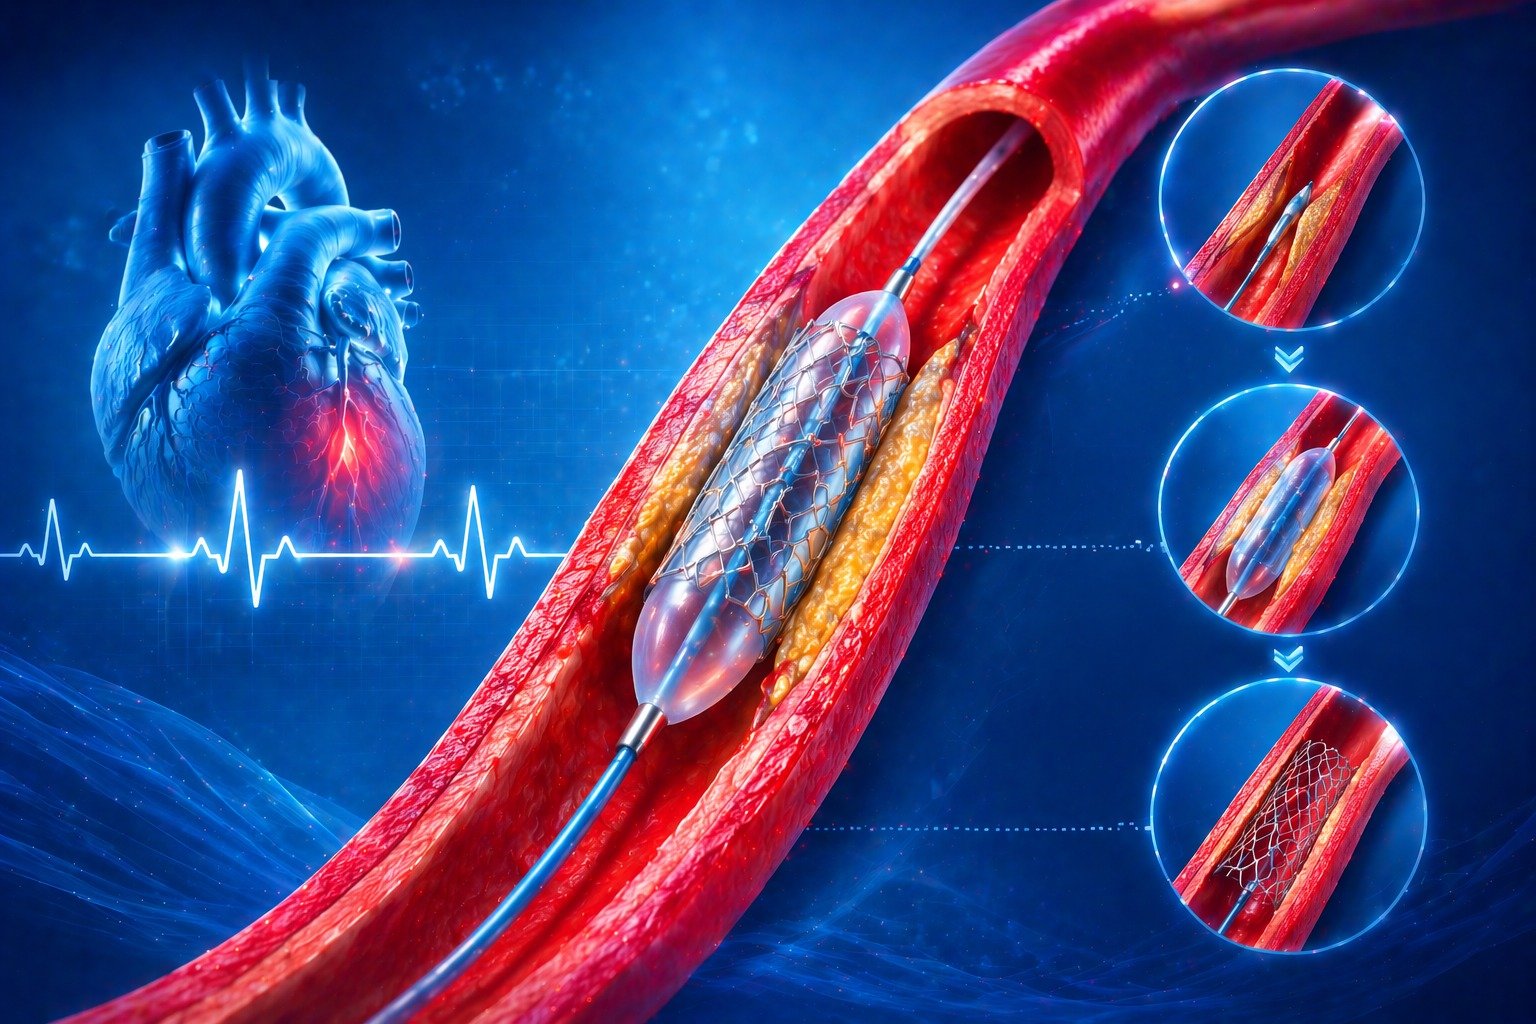

Interventions including Angiograms, Pacemaker Implantation, and Coronary Stenting.

Specialized stenting to restore blood flow with precision and monitoring for better heart function.

Specialized procedures including coronary, peripheral, and carotid stenting along with IVC filter devices.